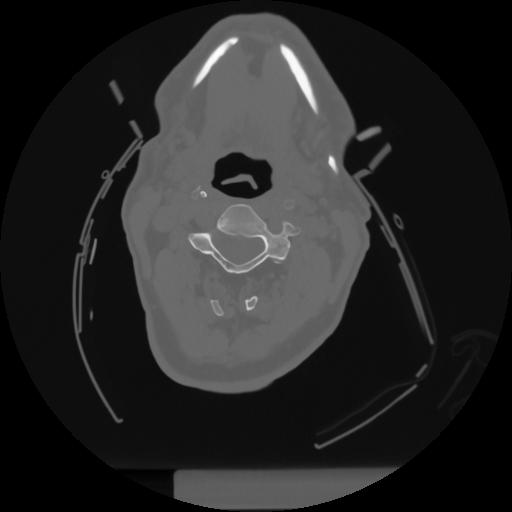

12 P.BLANDAS,,Vol,0.5,P.BLANDAS,,